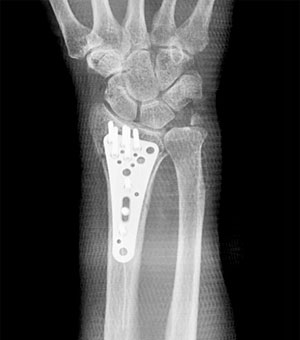

骨折後の手術例

コーレス骨折